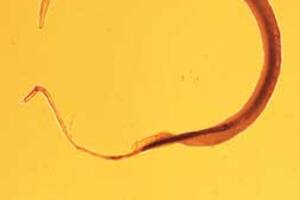

esquistosomiasis

Una vacuna contra la esquistosomiasis

La primera vacuna contra la enfermedad será probada este mismo año